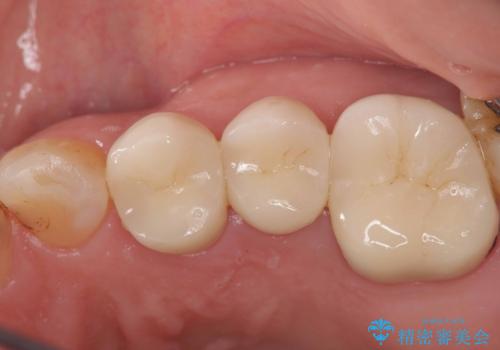

根管の中が空洞のままで被せ物と歯のきわも合っておらず適合が悪い状態でした。根尖部付近にはパーフォレーションリペア修復の痕がありました。バイオシーシーラーを使用しシングルポイント法で充填しました。空洞があると細菌が増える環境になってしまうので、根管治療からやり直し、緊密に充填しました。被せ物の見た目も大変満足していただけました。